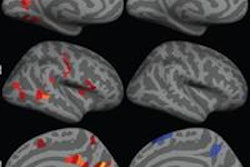

The combination of electroencephalography (EEG) and functional MRI (fMRI) leads to more precise localization of areas that cause epileptic seizures, giving neurosurgeons a better understanding of how to treat the condition, according to a study presented this week at the 2013 Canadian Neuroscience Meeting in Toronto.

Dr. Jean Gotman and colleagues from McGill University's Montreal Neurological Institute combined EEG, which provides information on the timing of the spikes but cannot always pinpoint location, with fMRI, which can better identify the location.

EEG-fMRI can be technically challenging because fMRI's strong magnetic field can interfere with the recording of the electrical currents emitted by brain cells. However, the two modalities can be useful for patients in whom precise localization of the seizure origin is difficult.

"Combing EEG and fMRI is a unique method to define noninvasively in the whole brain the regions involved in epileptic discharges," the authors wrote. "It is a complex tool, but it is likely to play an increasing role among the methods currently used to localize the source of epileptic activity."